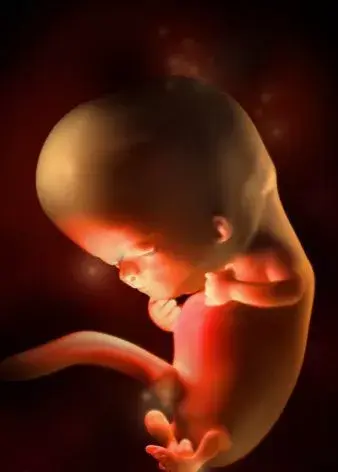

10周:

胎兒長到2.83厘米,胎兒各器官均已形成,胎盤雛形形成。B超可見胎囊開始消失,月芽形胎盤可見,胎兒活躍在羊水中 。形狀及大小像一個扁豆莢。胎兒的眼皮開始粘合在一起,直到27周以后才能完全睜開。手腳發育完成,手指和腳趾清晰可見,手臂更長而且肘部變得更加彎曲。胎兒的耳朵發育已經完成。

11周:

胎兒長到3.62厘米,胎兒各器官進一步發育,胎盤發育。B超可見胎囊完全消失,胎盤清晰可見。胎兒開始能做吸吮、吞咽和踢腿動作,胎兒的手指甲和絨毛狀的頭發等細微之處已經開始發育,維持胎兒生命的器官如肝臟、腎、腸、大腦以及呼吸器官也已開始工作。

12周:

胎兒長到4.58厘米,外生殖器初步發育,如有畸形可以表現,頭顱鈣化更趨完善。顱骨光環清楚,可測雙頂徑,明顯的畸形可以診斷,此后各臟器趨向完善。手指和腳趾已經完全分開,部分骨骼開始變得堅硬,并出現關節雛形。